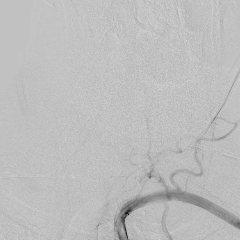

相逢就是缘,有求必全力以赴。立即进行全面评估,CTA和MRI发现颅内多发脑梗塞,脑干为重,双侧椎动脉颅内段基本看不到了,而进一步的DSA造影更为糟糕,左侧椎动脉的颅内颅外段直接全程完全闭塞,右侧颅外剩下一个小尾巴在血液中摇摇欲坠……,诺大的后循环仅仅靠纤细的后交通动脉从前循环借点血液过来,勉强续命,仅仅靠这点前循环的救急,可谓“杯水车薪”,不是“长久之计”,于是决定开通右侧闭塞的椎动脉(颅内+颅外,主要集中在V3+V4段)。